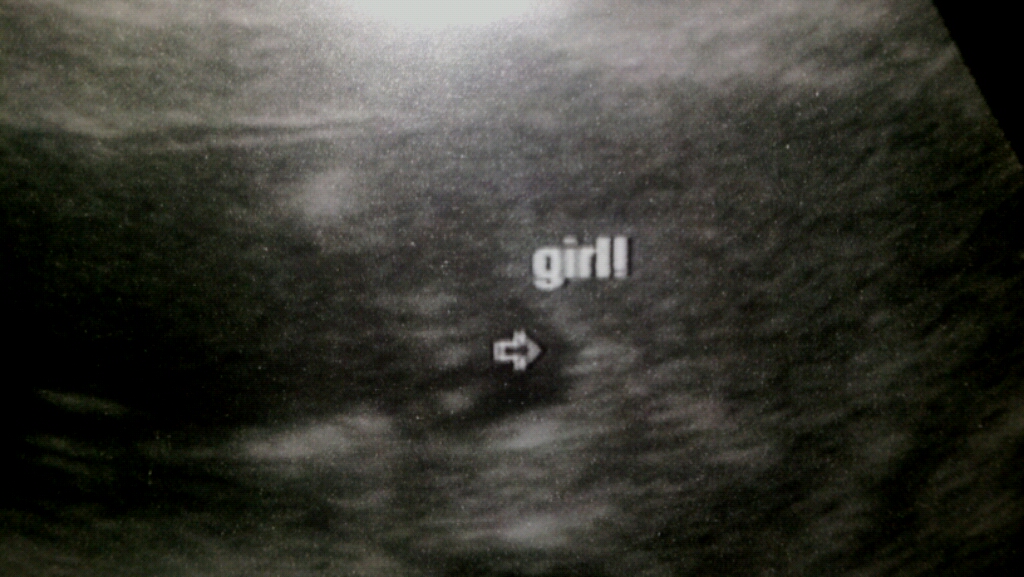

Update, 16 week ultrasound, tech was 99.9% sure it's a GIRL!!! I'm still in shock, but over the moon! Thanks everyone for all of your guesses!Attachment 7388

Very girly! Congrats!!!